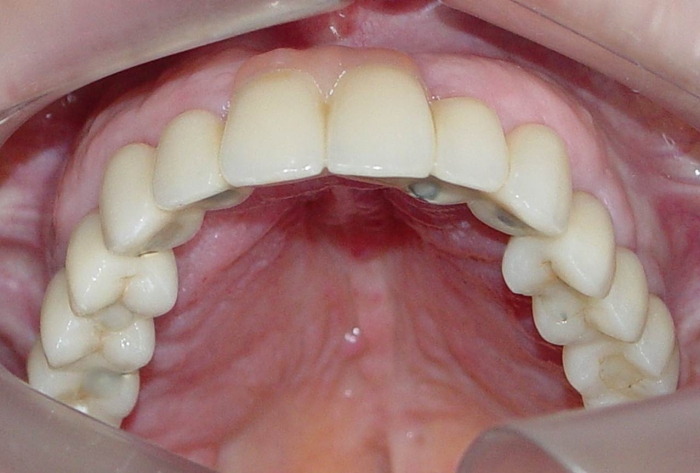

Imagens da prótese fixa superior em porcelana sobre implantes Cone Morse